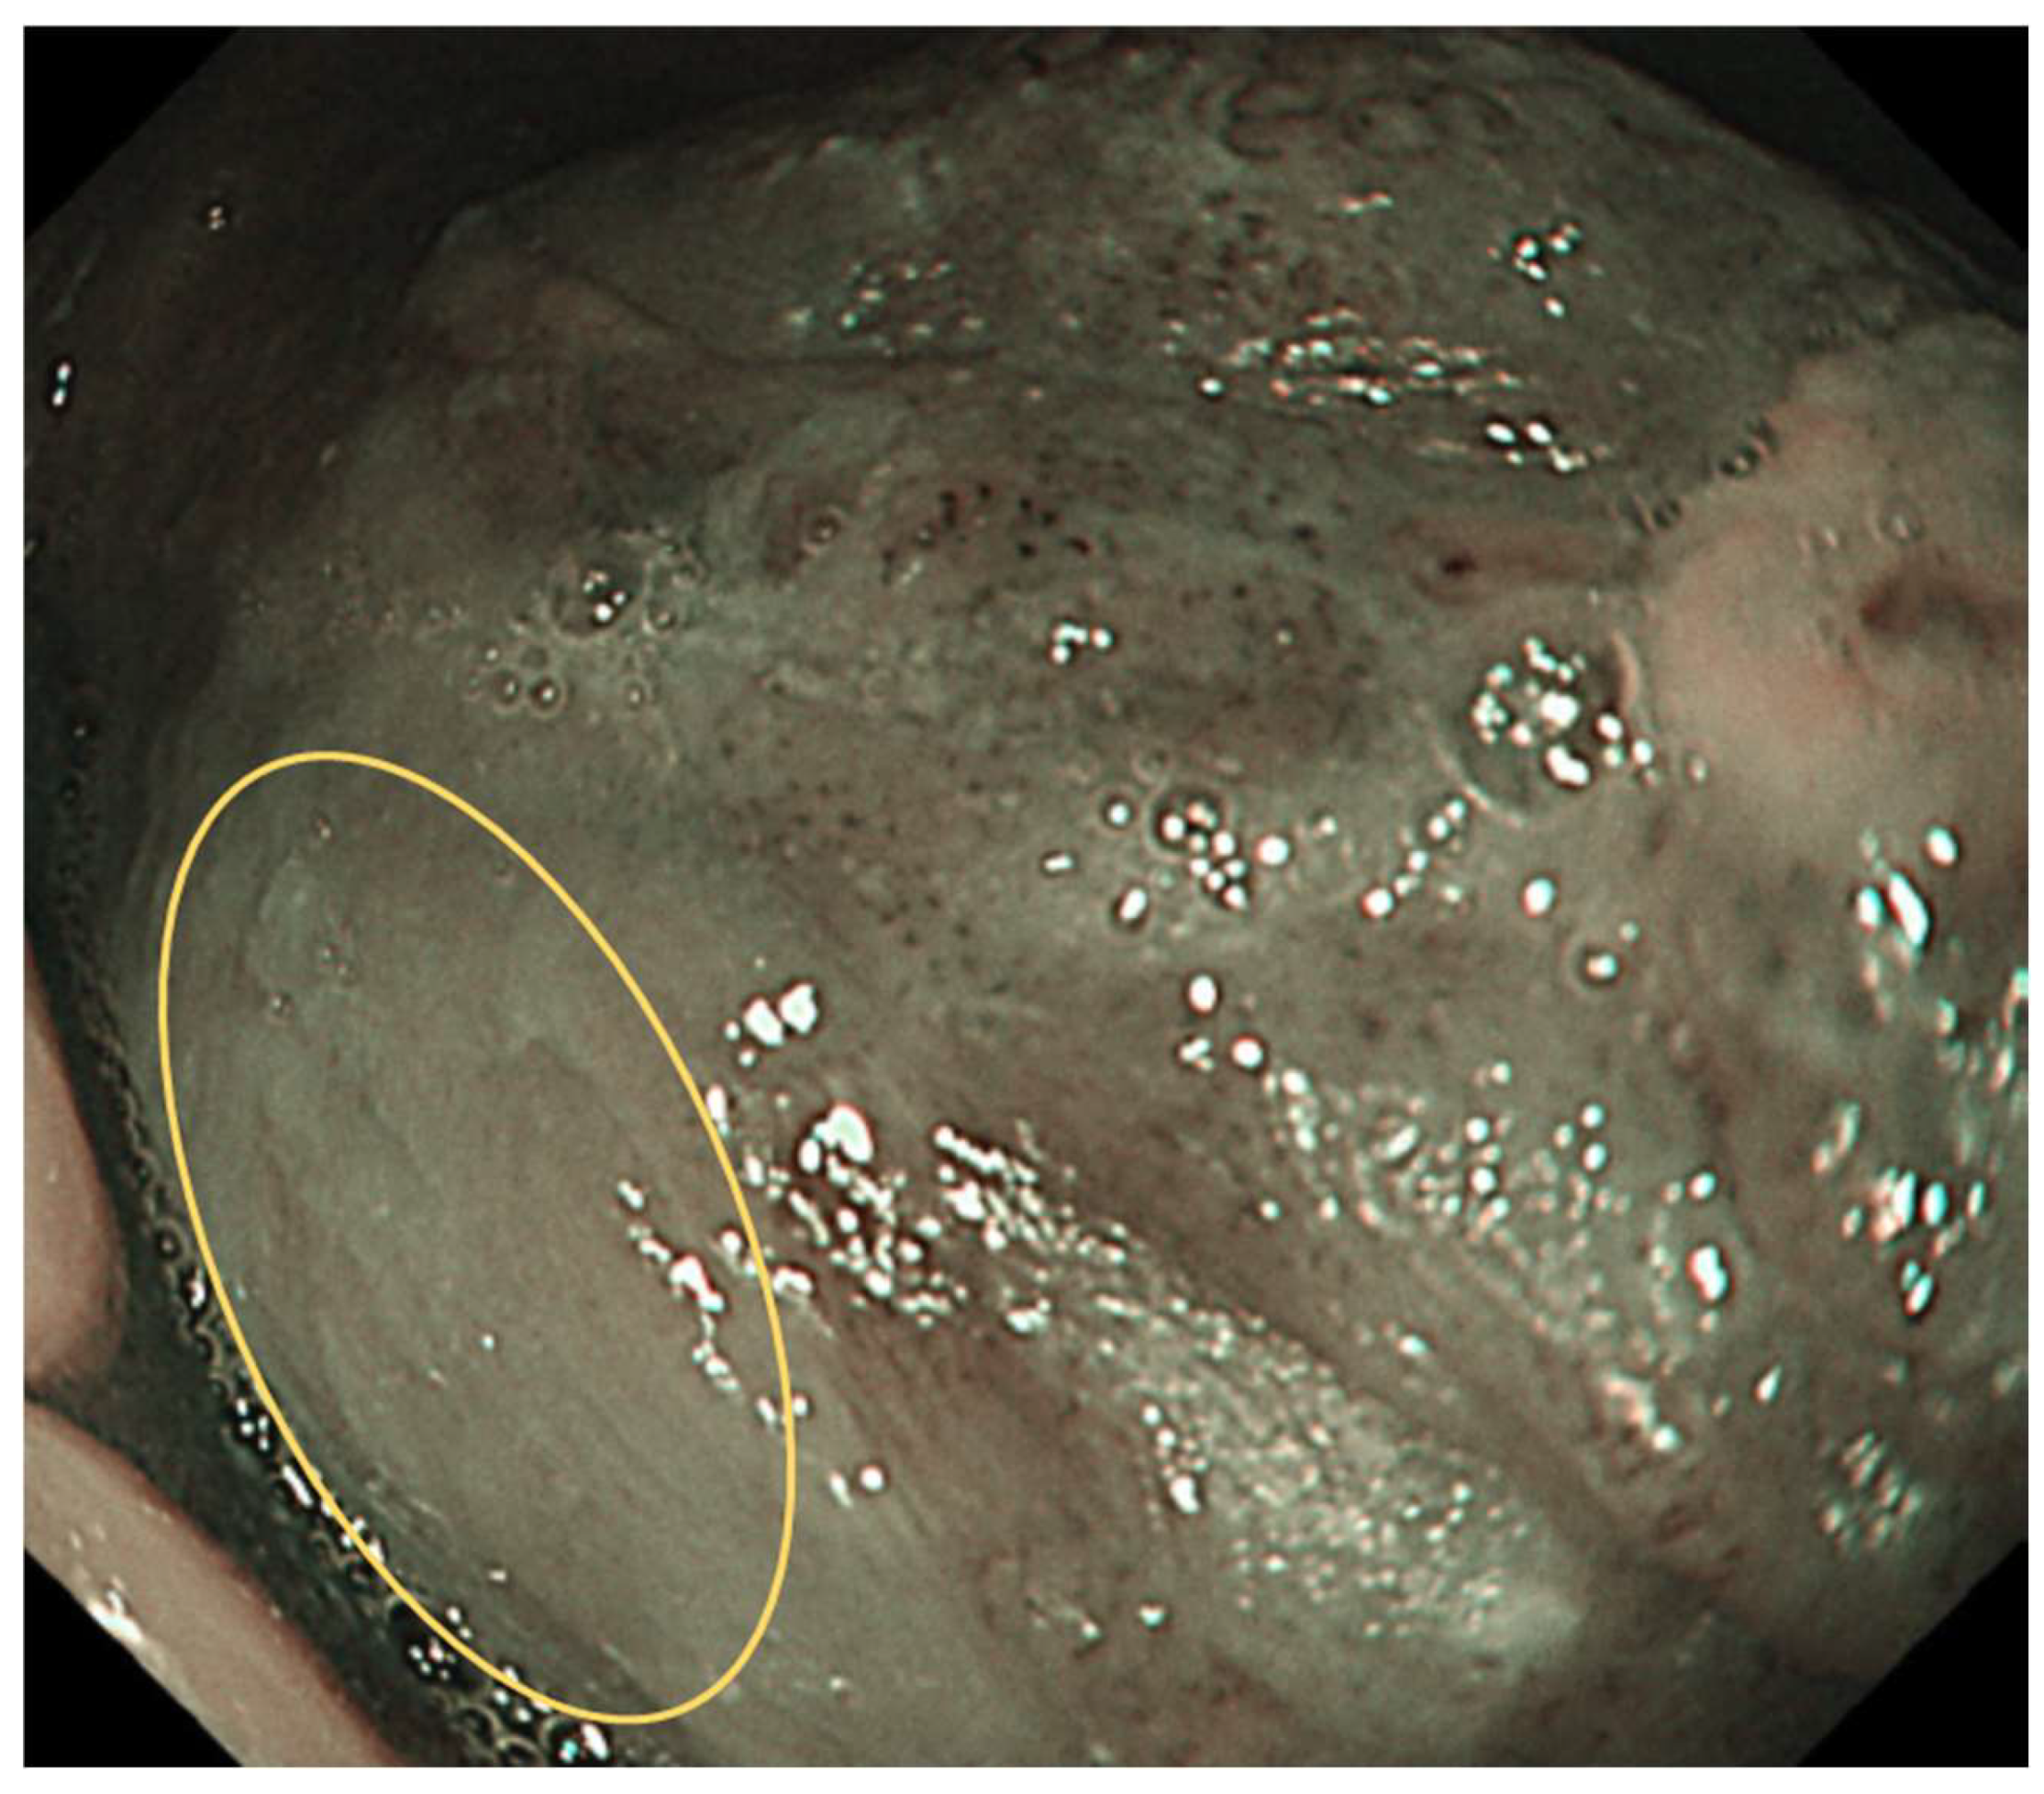

Type 0: No vessels are observed due to normal mucosa or keratinization (Figure 1).

Figure 1. Type 0: No vessels are observed due to normal mucosa or keratinisation, etc.